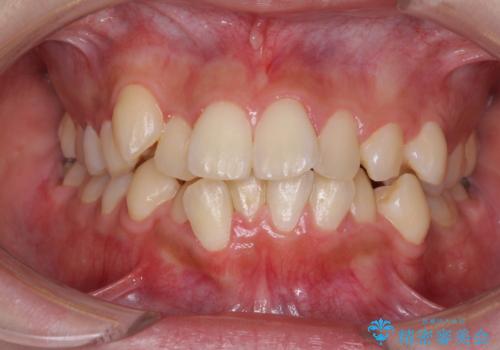

- 八重歯やデコボコをインビザラインで治療したいとのことで来院された患者様です。

インビザライン単体で治療を行うには叢生が強いと判断されたため、事前にワイヤー装置で抜歯矯正を行い、ある程度改善してからインビザラインにて仕上げていくこととしました。